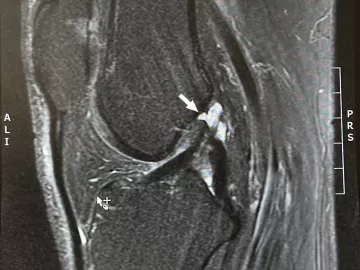

Rotator cuff issues can vary from mild strains to severe tears, posing treatment dilemmas. Massage can play a key role in conservative treatments if the therapy is well-designed and targeted to the client’s individual presentation.